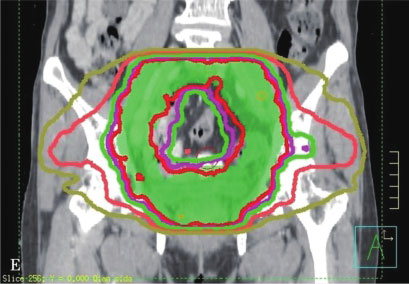

IMRT则是在3DCRT基础上的进一步发展,自1990年代早期IMRT被应用于临床以来,目前已成为一项常规开展的技术。IMRT通过多角度射野设置、多子野分割、滑窗等技术使均匀输出的通量分布变成不均匀分布,明显增加了靶区的剂量适形性,以避免或减少正常组织的照射,最大限度地限制治疗的副作用。IMRT的主要优势是其对凹凸靶区的适形能力,特别是凹面邻近重要器官时尤有优势。据估计,临床治疗的PTV有30%是凹形的靶区,因此可以从IMRT明显获益。另一方面,IMRT治疗方案是在治疗计划系统内通过逆向治疗计划的设计而得到,可以获得较正向计划方法更优的靶区适形性和更窄的侧向半影。通过调节每个射野的通量强度,在肿瘤靶区和正常器官之间形成一个很窄的剂量梯度,通常允许至少95%的PTV接受规定的处方剂量,同时保证周围正常组织的受量在既定的耐受范围之内。图7-2-1为IMRT与3DCRT技术的剂量分布图,其中图A、B、C所示为3DCRT剂量分布,图D、E、F所示为IMRT剂量分布,其中IMRT的剂量靶区适形性明显优于3D-CRT。

图7-2-1 IMRT与3DCRT技术的剂量分布图

A~C.为3DCRT剂量分布;D~F.为IMRT剂量分布